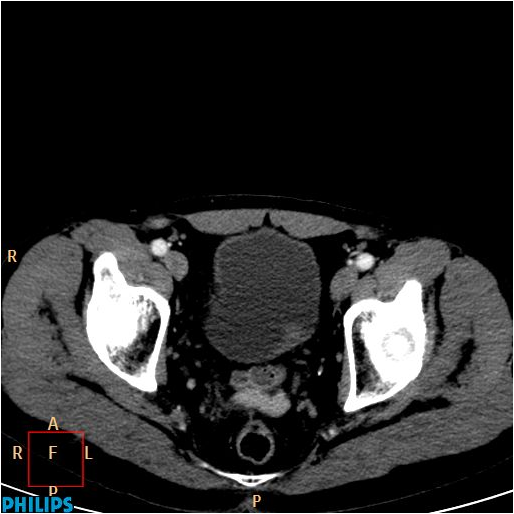

Image

Figure 9. Axial CT images show an extensive tumor in the bladder fundus.